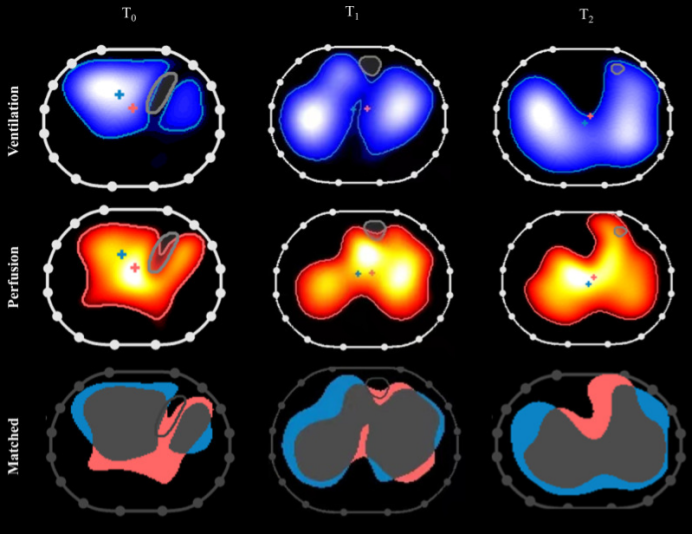

5)俯卧位通气监测:俯卧位通气在临床中备受关注且展现出显著效果,借助EIT技术可以清晰阐释其作用机制:随着俯卧位通气时间的延长,EIT监测显示肺内气体分布逐渐趋于均匀,同时血流灌注也得到改善(图13)。当气体分布与血流灌注二者协同优化,通气血流比值(V/Q)愈发匹配,呼吸功能随之改善。EIT能够实时、精准捕捉肺内通气与血流的动态变化。

图片

13  俯卧位对患者通气-灌注匹配的影响

图源:Crit Care, 2022, 26(1):154.